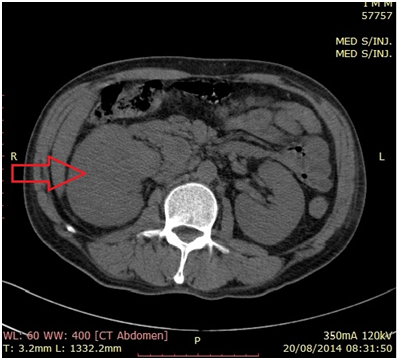

Mr RAV. 53 years old, no smoking was hospitalized for progressive worsening of dyspnea lasting for 6 months, accompanied by chest pain basi-left. In the interview we noted a notion regularly taking a decoction of clinical médicinales. L'examen virtues plants entering found an alteration of the general status (PS=3 according to WHO), a left pulmonary syndrome without condensation fever. Radiography of thorax face showed pleural thickening picture left scalloped. Chest CT (Figure 1) confirmed the pleural lesions secondary look and abdominopelvic CT scan for staging (Figure 2) found a retroperitoneal mass compatible of renal tumor primitive right. Biologically, there was a LDH assay was raised to 1423 IU/ml (5 times normal). Histological examination of a biopsy transthoracic puncture confirmed the location of a secondary urothelial carcinoma at the pleura (pT4N2M1) (Figure 3). Our patient had received a course of BCG instillation Pasteur by percutaneous nephrostomy and the tear-X (thoracic drainage system) and died after three months of decline following the natural evolution of the tumor.

Figure 2 Abdominal CT scan showing UTUC infiltrating the renal parenchyma, and wich is also for staging.